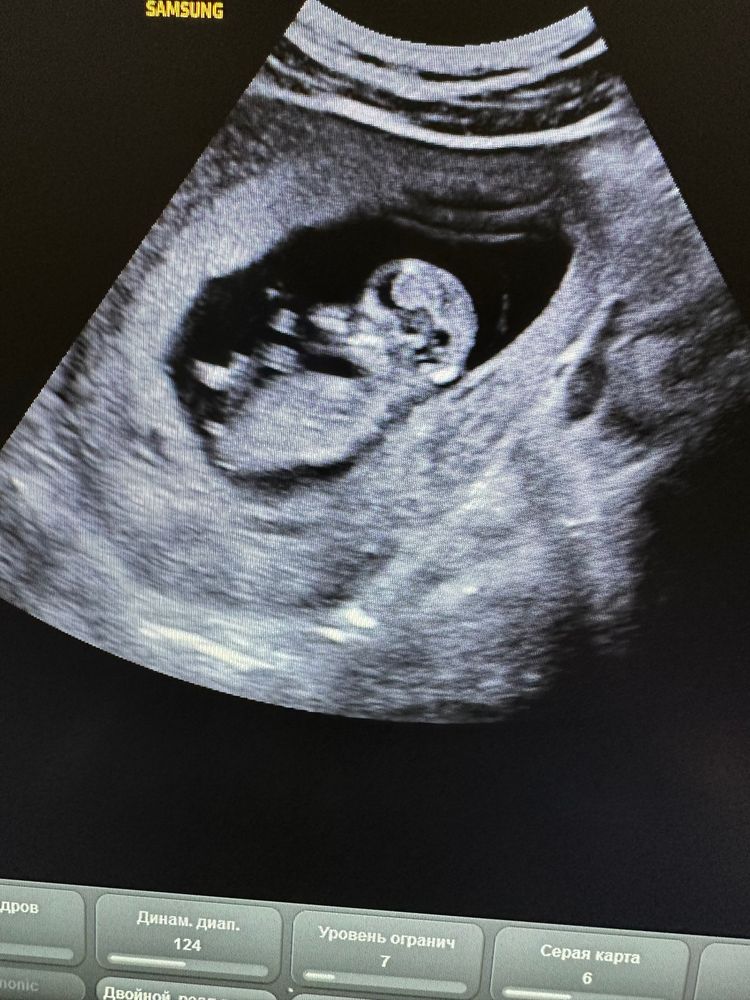

Половой бугорок. Первый скрининг

Осмотр в беременность, вопросыДевочки, ну что! Кто что видит?

тут нам 12 недель поставили. КТР 58 мм. Ручки ножки, очень активненько пузеныш двигается. Узи делали два через день. Поэтому картинки разные.

На верхнем девочка, на нижнем мальчик! Я угадала? 🤣

Кто бы что не видел- это не имеет никакого значения. На вашем сроке половые органы ребёнка недифференцированы, и положение полового бугорка еще среднее. Через две недели будет возможно предположить более обоснованно.